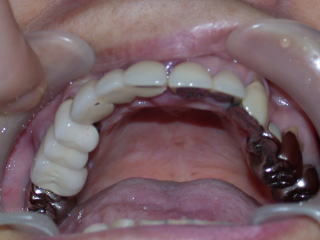

アバットメントの方向位置が狂わないようにジグを当てて、アバットメントを装着します。

上部構造物作製、試適、調整し装着しました。